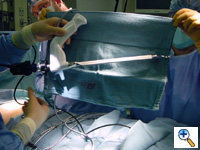

![]() |

| Figure 6. The endoscopic tunneler is the same instrument used in our adult cardiac program for endoscopic saphenous vein procurement. |

We utilize the endoscopic saphenous vein harvesting equipment from our adult cardiac program to create the tunnels endoscopically, under visual guidance (Figure 6). We have found similarity between the tunnel necessary for endoscopic saphenous vein harvesting and the tunnels for minimally invasive pectus repair and we feel that the improved visualization afforded by this technique might decrease the potential for cardiac or mammary artery injury during minimally invasive pectus repair.